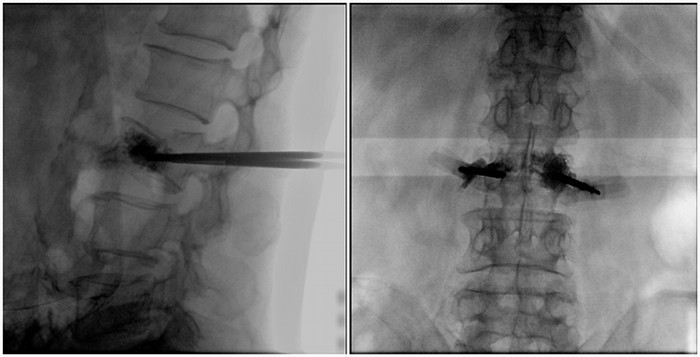

普愛醫(yī)療大平板一體式移動(dòng)C臂采用30cm×30cm的平板探測(cè)器,能在手術(shù)過程中,為醫(yī)生提供更廣闊的視野范圍,帶給醫(yī)生更全面的影像信息。在進(jìn)行脊柱類手術(shù)時(shí),一次曝光即可呈現(xiàn)全節(jié)段腰椎,避免因?yàn)槌氏癫蝗鴮?dǎo)致重復(fù)曝光,不僅提高了手術(shù)效率,而且避免醫(yī)生吸收過量的輻射。